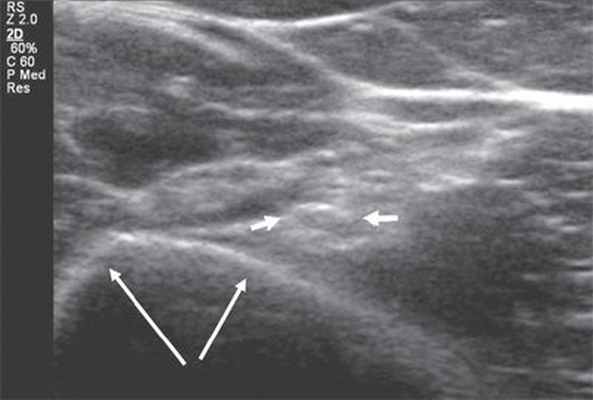

Ультразвуковое исследование периферических нервов целесообразно начинать с поперечной проекции в точке, где нервный ствол легче всего идентифицировать, смещаясь затем в проксимальном и дистальном направлениях, оценивая структуру нерва на протяжении 3.

Изображение нерва имеет ряд характерных признаков. В поперечной проекции он выглядит как овальное или округлое образование с четким гиперэхогенным контуром и внутренней гетерогенной упорядоченной структурой ("соль - перец", "медовые соты") [4, 6, 7]. В продольной проекции нерв лоцируется в виде линейной структуры с четким эхогенным контуром, в составе которой правильно чередуются гипо- и гиперэхогенные полосы - "электрический кабель" [7]. Толщина периферических нервов вариабельна и составляет от 1 мм для пальцевых нервов до 8 мм для седалищного нерва.

Рис. 1. Поперечная сонограмма лучевого нерва (короткие стрелки) на уровне спирального канала плечевой кости (длинные стрелки - контур плечевой кости).